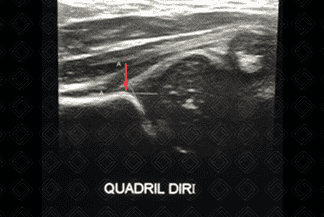

FIGURAS 1 e 2 Figuras 1 e 2. Créditos: Dra. Elazir Mota - Rio de Janeiro/RJ

Descrição das imagens: Ultrassonografia do quadril (lactente de 2 meses). Estudo normal (ângulo alfa mede 62 bilateralmente). Observar a medida do ângulo alfa e traçar uma linha paralela ao ilíaco, tangenciando o promontório (seta vermelha - figura 1) e outra tangenciado o teto ósseo (seta branca - figura 2). Valor normal do ângulo alfa maior ou igual a 60.

1. Ultrassonografia de quadril: Exame de escolha até 3-4 meses de vida. O quadril do bebê deve ser avaliado por radiologista pediátrico experiente. São avaliados morfologia do promontório, teto ósseo e cartilaginoso, posição da cabeça femoral e presença de deslocamento. Além disso, como rotina, avalia-se o ângulo alfa (linha traçada entre teto ósseo e promontório). Valor normal: ≥ 60º.